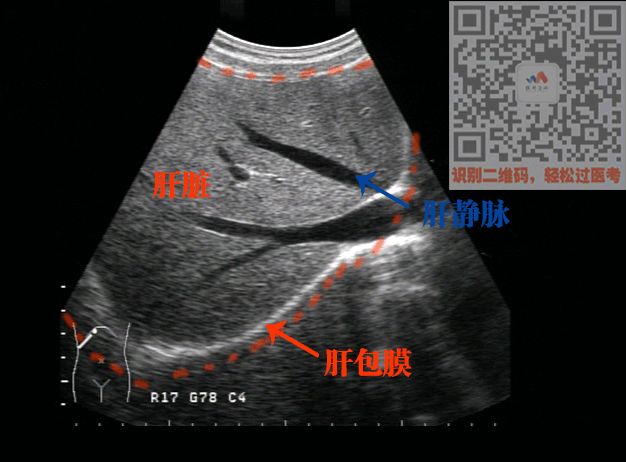

2,正常声像图 肝脏的形态,大小,包膜,回声,管道结构